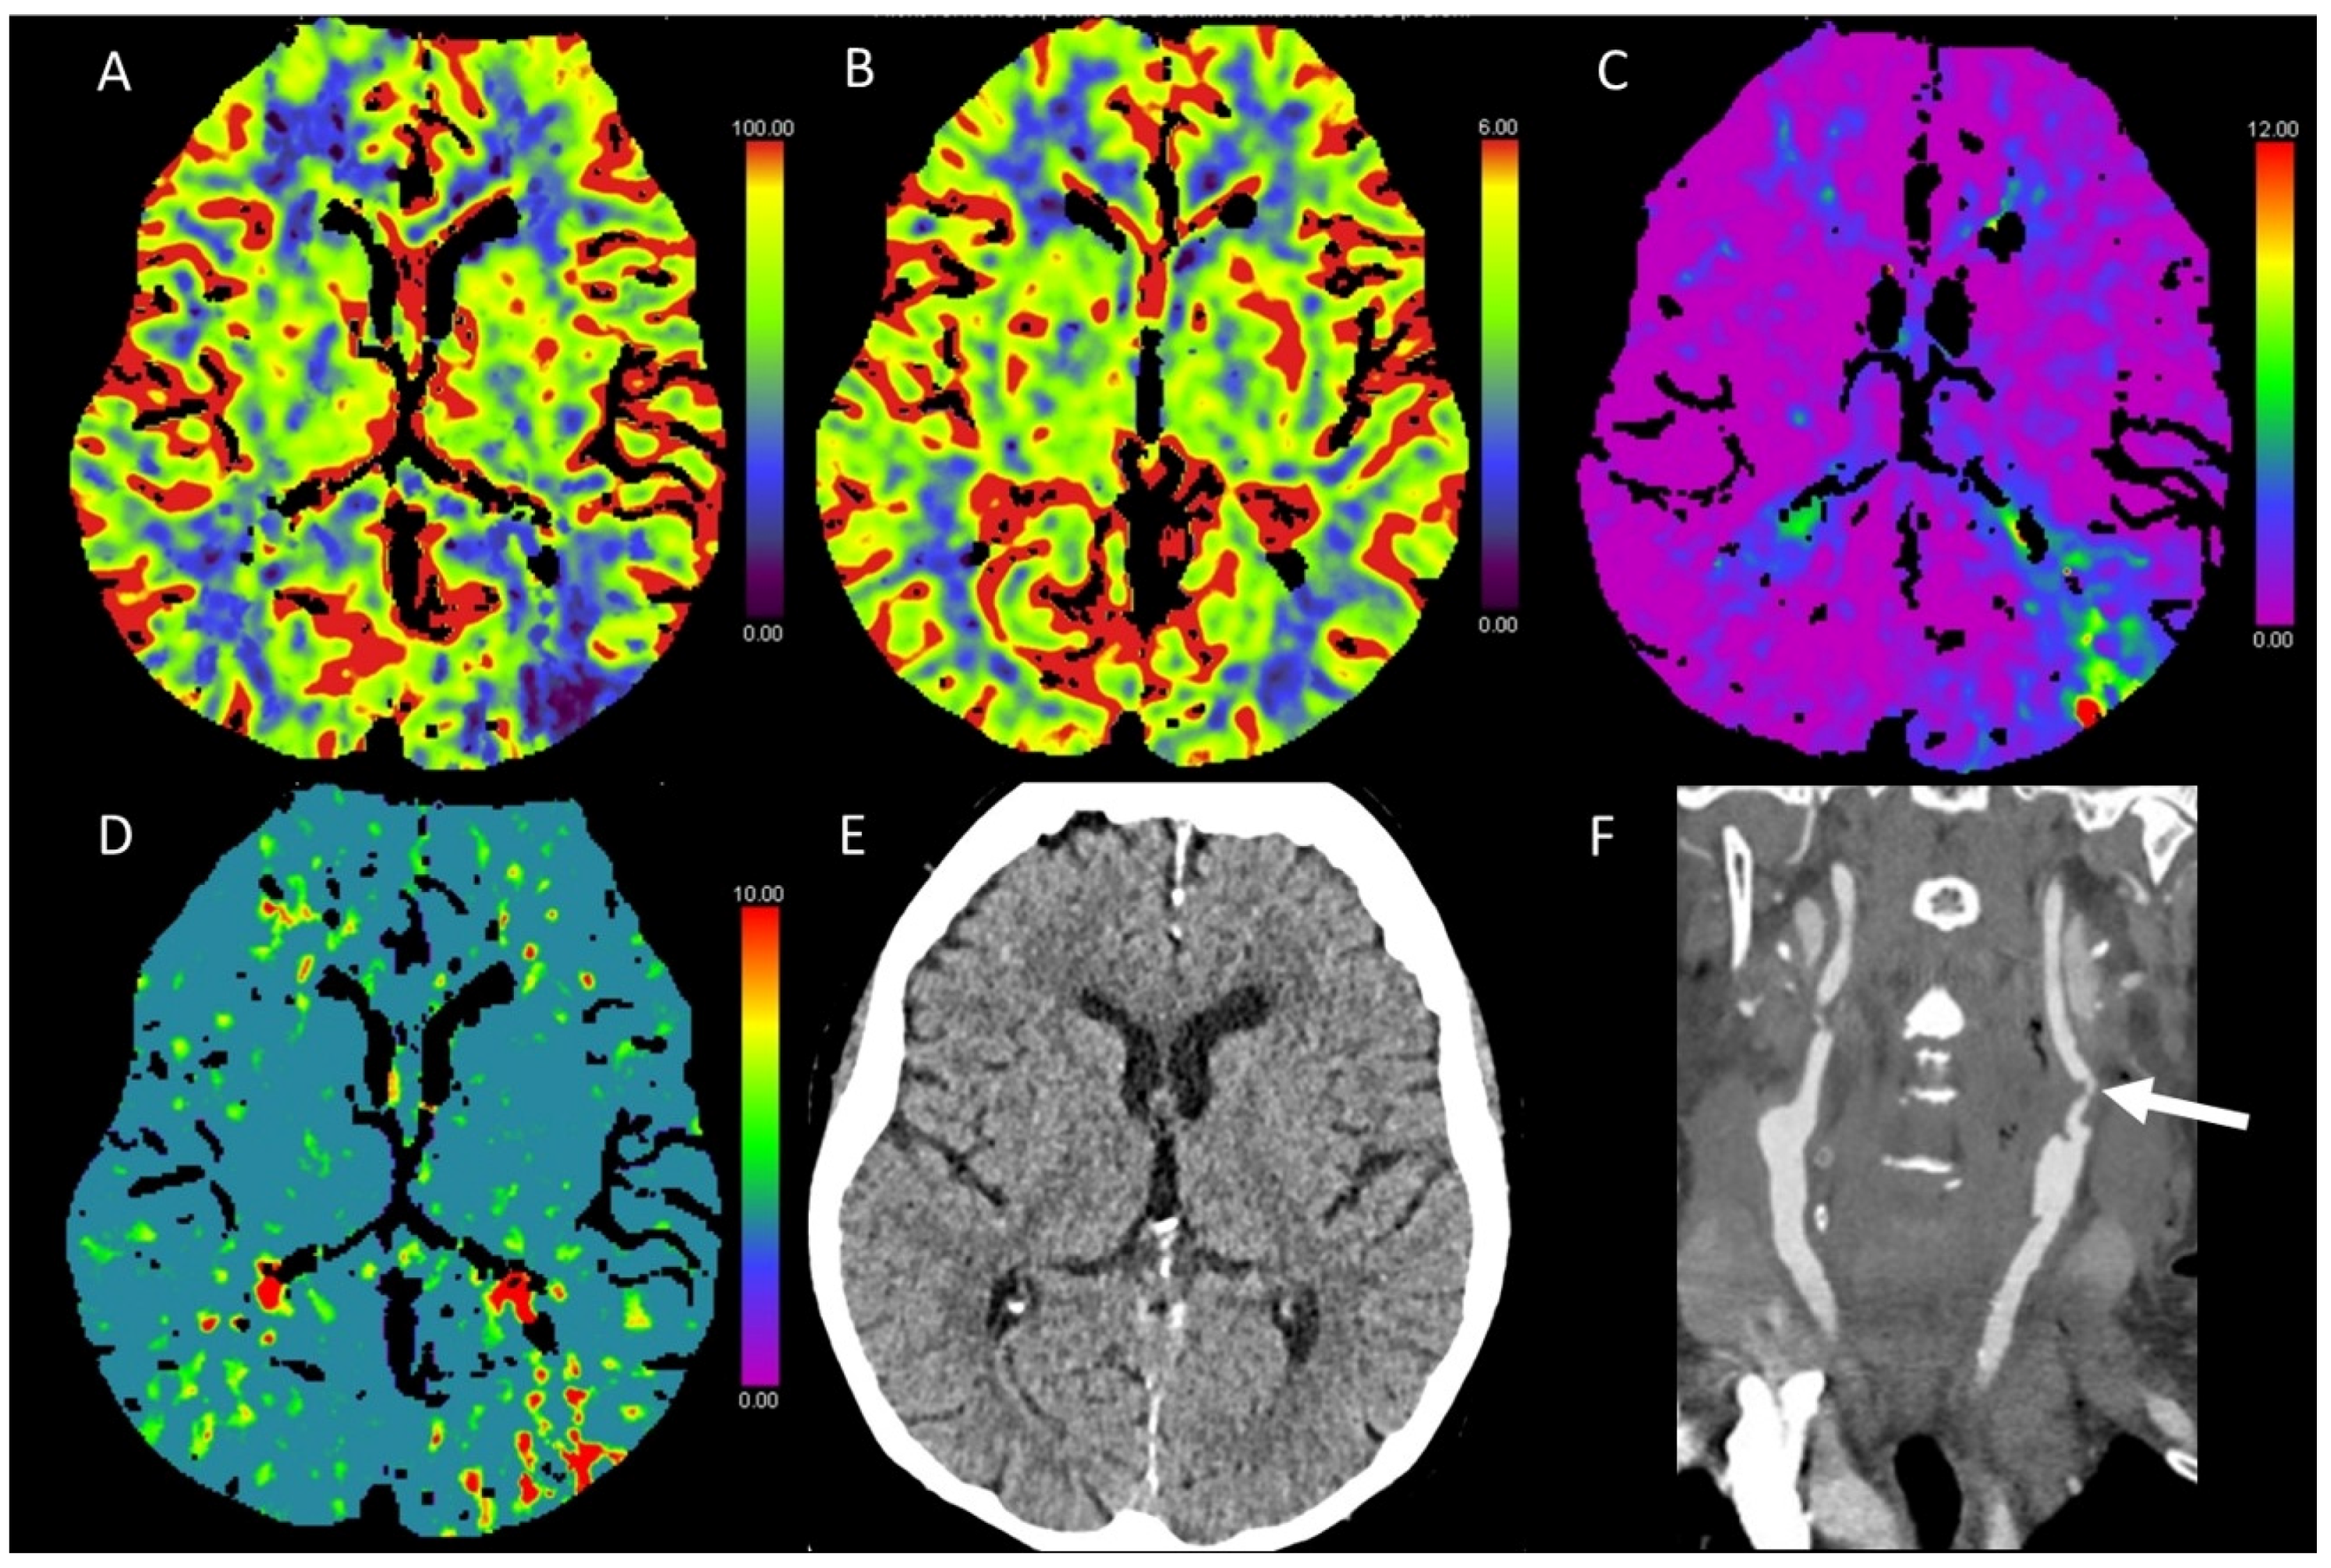

3.5. Hypotensive Cerebral Infarction (HCI) with Watershed Infarcts/Border Zones

- Siemund, R.; Cronqvist, M.; Andsberg, G.; Ramgren, B.; Knutsson, L.; Holtas, S. Cerebral perfusion imaging in hemodynamic stroke: Be aware of the pattern. Interv. Neuroradiol. 2009, 15, 385–394. [Google Scholar] [CrossRef]